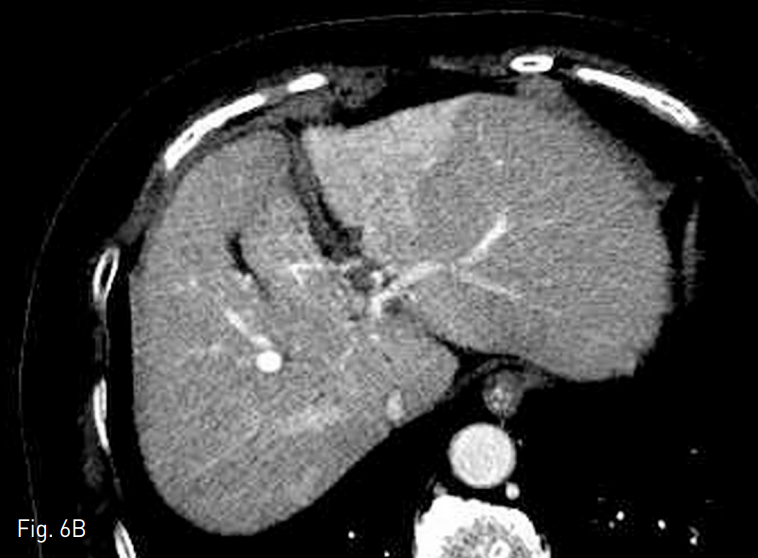

Fig. 6. Computed tomography obtained at 11 months after transarterial radioembolization.

A. Main tumor size is decreased from 7.5cm to 1.8cm.

B. The amount of tumor thrombosis in portal vein is decreased.